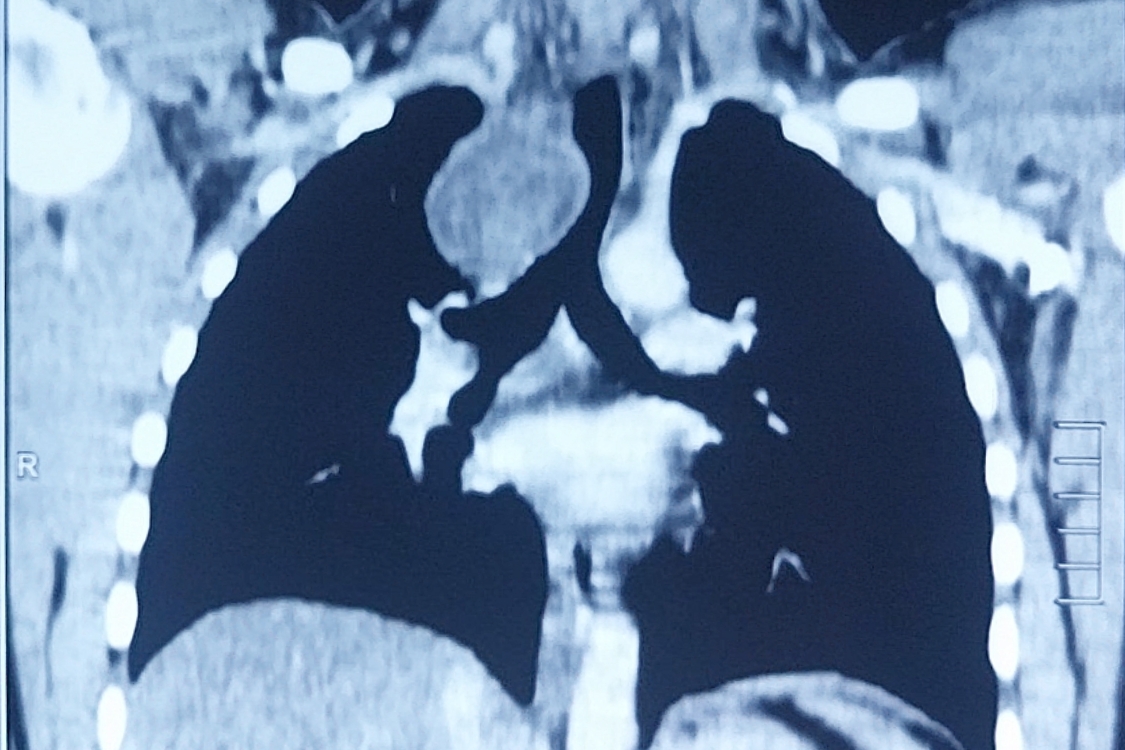

Figure 2. CECT of the chest showing a round homogenous cystic lesion in the right paratracheal region pressing on the esophagus and trachea.

A 16-year-old boy presented with chest pain for the previous seven days that was more on the right side, gradual in onset, dull in character, intermittent, and radiating to the back. It was aggravated on exertion and was relieved with rest. The pain was associated with shortness of breath. The patient also complained of dysphagia, which was occasional and progressive. There was no history of cough or recent chest infection. General physical and systemic examinations were unremarkable. He had a low-grade fever with a hemoglobin of 13.5 g/dl, white cell count of 12.4/dL, and ESR of 52. Other routine lab investigations were within normal limits. His chest x-ray showed a right mediastinal round opacity on the right side of the carina. On his CECT scan Chest, the authors found a well-marginated nonenhancing thick fluid-attenuating lesion centered at the right paratracheal location in the middle and posterior mediastinum on the right side that was pressing on the esophagus and trachea.

The patient was diagnosed as having a bronchogenic cyst. The authors decided to treat the patient surgically. The patient underwent a right-sided posterolateral thoracotomy via the fifth intercostal space. A round, smooth, uniform, soft, cystic mass in the posterior mediastinum was found, measuring 3.5 x 2 x 3 cm. The mass was extrapleural, adherent to the esophagus and trachea posteromedially, to the apical lobe of the lung anterolaterally, and to the azygous vein inferiorly. The pleural layer was peeled off the mass. The mass was dissected free from surrounding structures and was found to be growing from the right main bronchus from a pedicle. The pedicle was found to be cartilaginous on palpation. The pedicle was ligated, and the mass was excised. The pleura was closed back with Vicryl sutures. The chest cavity was washed with normal saline and checked for air leak. Two chest tubes were placed: posteroapically and posterobasally. Routine chest closure was performed. The patient was extubated and subsequently shifted to the ward in stable condition. Postoperatively, chest x-ray showed a fully expanded lung with no residual opacity. On the second postoperative day, the chest tubes were removed and the patient was discharged.